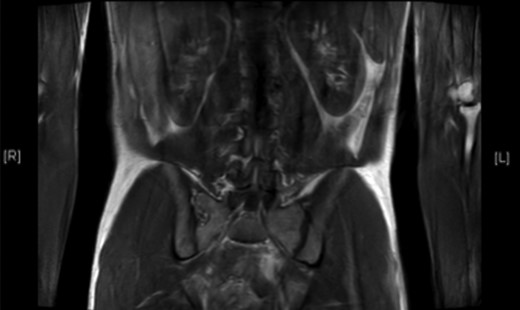

A 26-year-old male, with a family history of PGL4, presented with an 18-month history of paroxysmal headaches, a one-month history of frequent diaphoresis, anxiety attacks and unintentional weight loss of one stone in two months. His father and brother had previously been diagnosed with PGL4 and had undergone surgical resections for abdominal and pelvic paragangliomas. He underwent biochemical and genetic work-up confirming significantly elevated plasma normetanephrines and 3-methoxytyramines, with normal plasma metadrenaline levels. Full body CT, MR (Fig. 1) and 18F-fluorodeoxyglucose positron emission tomography (FDG-PET) CT imaging (Fig. 2) revealed a left para-aortic mass in the mid abdomen and a mediastinal lesion located between the root of aorta and origin of the main pulmonary artery, encroaching the right ventricle.

T2-weighted MRI scan showing hyper-intense mass lying anterolateral to left side of aorta in mid-abdomen.